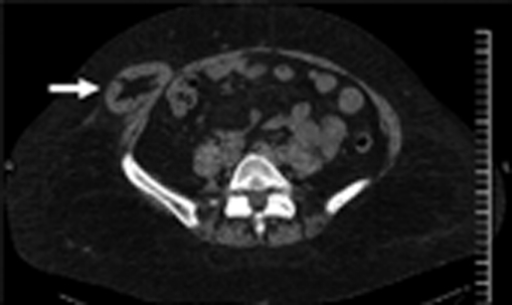

What's the Diagnosis?